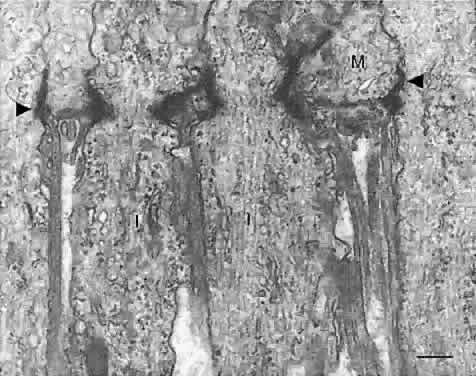

As described above, a thin membrane is apparent at the level of the photoreceptor inner segments (see Fig. 5B). This so-called membrane is actually a series of intermediate junctions (zonulae adherentes) between the rod and cone inner segments and the apical processes of the Müller cells (Figs. 12 and 13). These junctions constitute the inner border of the subretinal space and are a barrier to diffusion of large molecules into and out of this space.7

Fig. 12. The external limiting membrane is formed by continuous bands of intermediate junctions (zonulae adherentes) seen here in meridional section. The inner segments (I) of the photoreceptors are linked to Müller cell processes (M) by the intermediate junctions (arrowheads). Bar = 0.5 μm. (Hogan MJ, Alvarado JA, Weddell JE: Histology of the Human Eye. Philadelphia: WB Saunders, 1971.)

Fig. 13. A tangential section through the external limiting membrane of human retina. Note continuous belts of intermediate junctions (arrowheads) between the photoreceptor inner segments (I) and Müller cell processes (M). Bar = 1.0 μm. (Hogan MJ, Alvarado JA, Weddell JE: Histology of the Human Eye. Philadelphia: WB Saunders, 1971.)